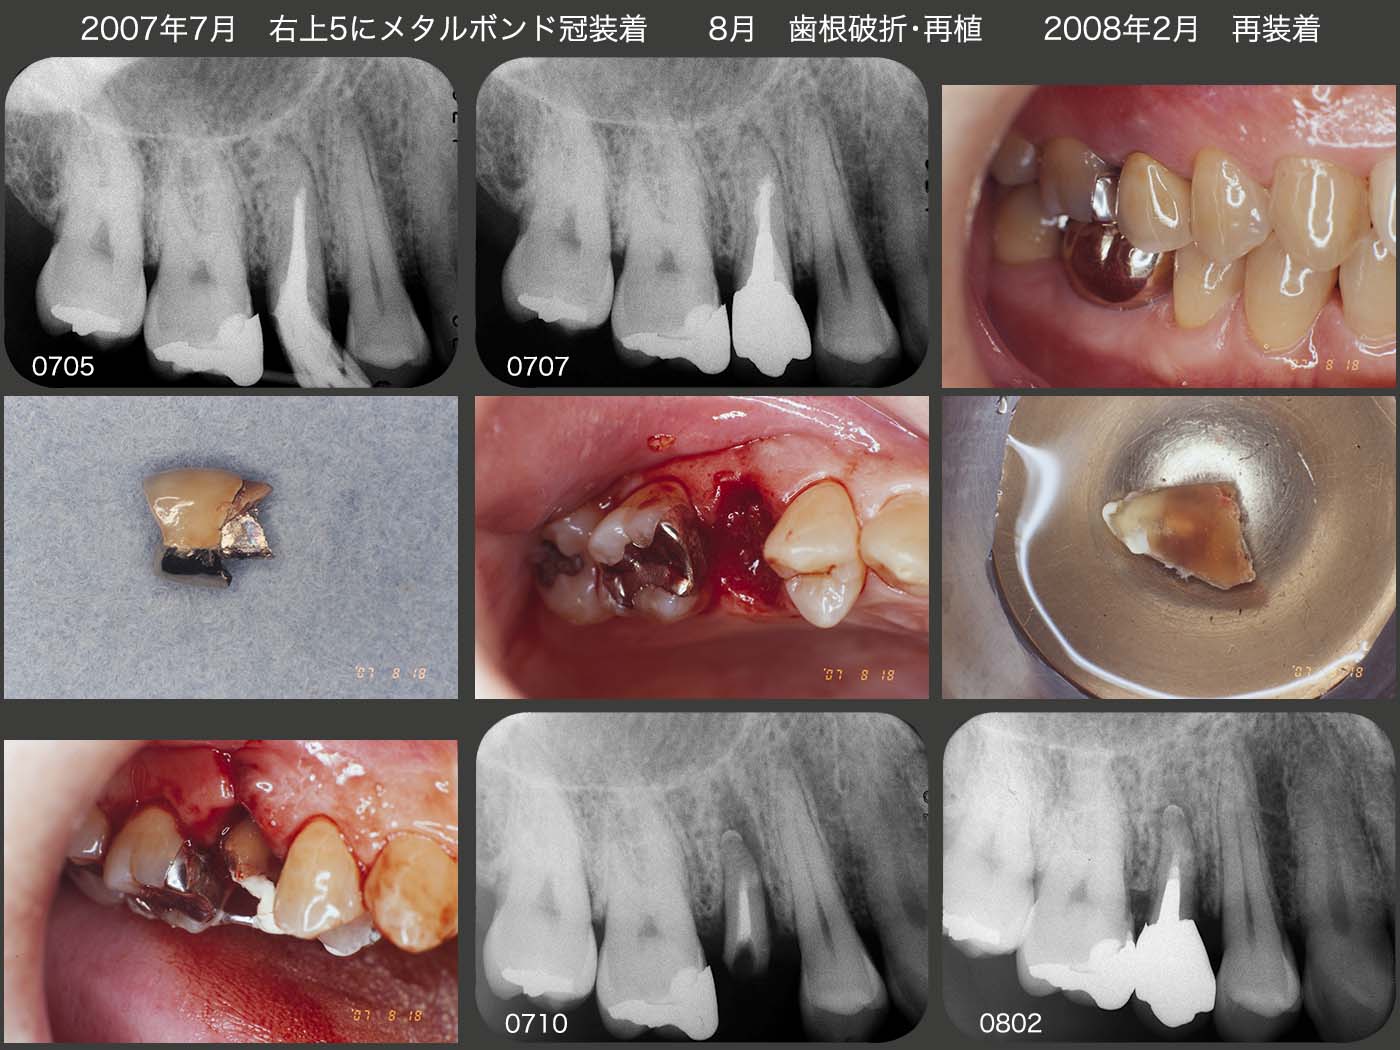

2007年4月,右上5がコアごと脱離した.念のため感染根管処置を行ったが,根尖まで穿通することはできなかった.7月にメタルボンド冠を装着した.しかし,何と8月に歯根破折してしまった.ここで本来は矯正的挺出を行うが,根尖に不安があったのでこの時は再植を選択した.実際,根尖付近に私が開けてしまったのか人工的穿孔が認められた.08年2月,再度メタルボンド冠を装着した.